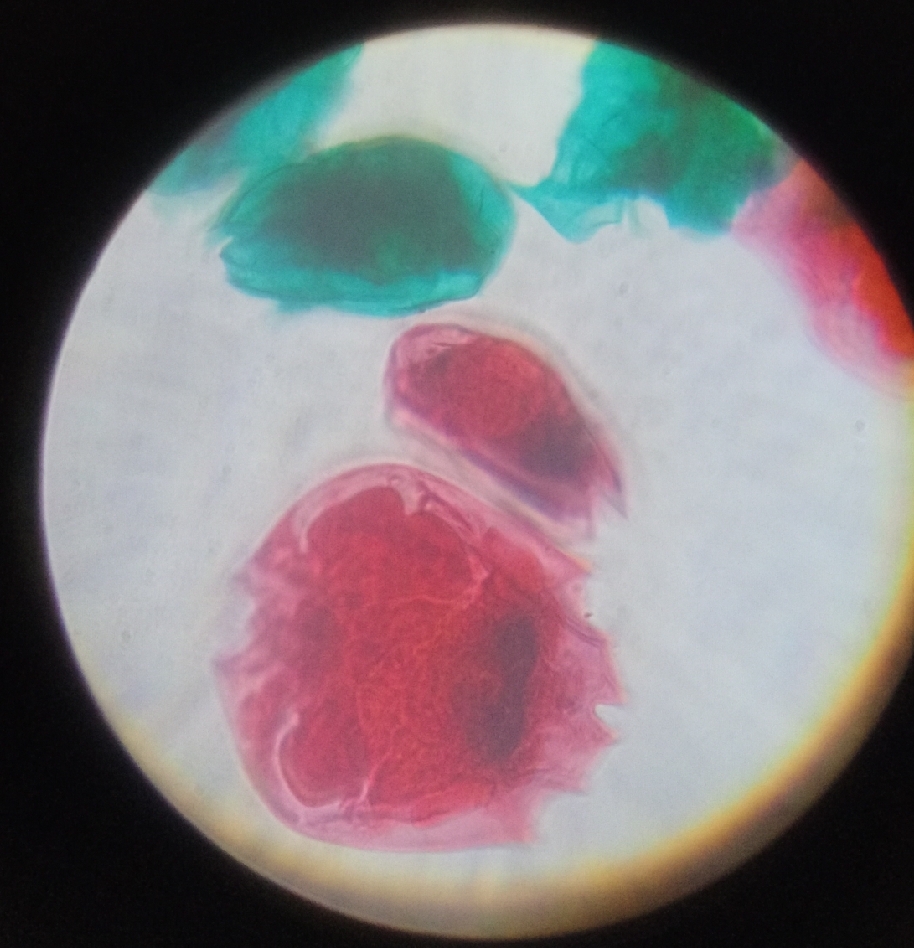

Its name comes from Ancient Greek plásma meaning “something molded” and the suffix -ōdēs meaning “like” or “resembling,” referring to its amorphous, shape-shifting form during its life cycle stages. This etymology reflects the parasite’s ability to adapt morphologically as it transitions between mosquito and vertebrate hosts.

Plasmodium spp. (malaria) in blood smear